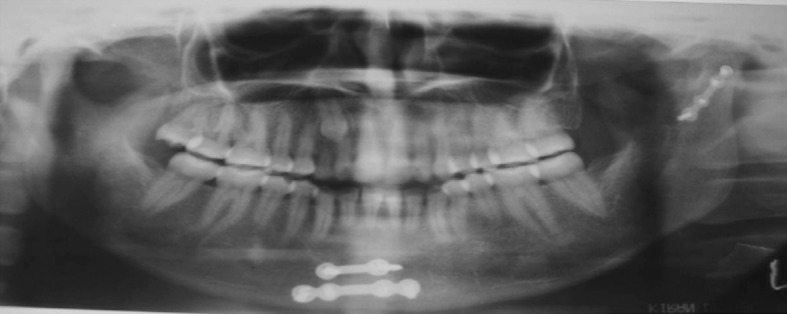

Fig. 5.

6 month post operative OPG

Radiographic examination revealed proper approximation of fracture fragments with good bone healing (Figs. 5 and 10), no evidence of plate exposure and screw loosening except in one case in preauricular approach. Sign of condylar resorption was seen in two cases after 3 months and complete resorption after 6 months in preauricular approach, whereas none in retromandibular approach (Figs. 1, 4, 6, and 9).